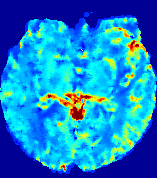

LesionRefer to captionRefer to captionRefer to captionRefer to captionRefer to captionRefer to caption𝐕rgbsubscript𝐕𝑟𝑔𝑏{\bf{V}}_{rgb}Refer to captionRefer to captionRefer to captionRefer to captionRefer to captionRefer to caption𝐕2subscriptnorm𝐕2{\|\bf{V}}\|_{2}Refer to captionRefer to captionRefer to captionRefer to captionRefer to captionRefer to captionRefer to caption3.53.53.52.82.82.82.12.12.11.41.41.40.70.70.70.00.00.0(mm/s)𝑚𝑚𝑠(mm/s)D𝐷DRefer to captionRefer to captionRefer to captionRefer to captionRefer to captionRefer to captionRefer to caption0.0200.0200.0200.0160.0160.0160.0120.0120.0120.0080.0080.0080.0040.0040.0040.0000.0000.000(mm2/s)𝑚superscript𝑚2𝑠(mm^{2}/s)Slice #1Slice #2Slice #3Slice #4Slice #5Slice #6

Figure 4: PIANO feature maps for another patient in the ISLES 2017 training set, where the lesion is located in the right hemisphere. Top row: segmented stroke lesion region (white) on different slices. The corresponding slices for the PIANO feature maps are shown in the following rows.

For a better insight into an estimated velocity field 𝐕𝐕{\bf{V}} and diffusion field 𝐃𝐃{\bf{D}}, we compute the following maps: (1) 𝐕rgbsubscript𝐕𝑟𝑔𝑏{\bf{V}}_{rgb}: Color-coded orientation map of 𝐕=(Vx,Vy,Vz)T𝐕superscriptsuperscript𝑉𝑥superscript𝑉𝑦superscript𝑉𝑧𝑇{\bf{V}}=(V^{x},V^{y},V^{z})^{T}, obtained by normalizing 𝐕𝐕{\bf{V}} to unit length and mapping its 3 components to red, green, blue respectively; (2) 𝐕2subscriptnorm𝐕2\|{\bf{V}}\|_{2}: 222 norm of 𝐕𝐕{\bf{V}}; (3) D𝐷D: scalar field in Eq. 5.

Fig. 3 and Fig. 4 show the PIANO feature maps estimated from two ISLES 2017 patients: all are highly consistent with the lesion in both cases. Details of the blood flow trajectories are revealed in 𝐕rgbsubscript𝐕𝑟𝑔𝑏{\bf{V}}_{rgb} by the ridged patterns and the sharp changes of colors in the unaffected (right) hemisphere, while the flat patterns appearing within the lesion provide little directional information about the velocity and indicate low velocity magnitudes. Velocity magnitudes are more directly visualized via 𝐕2subscriptnorm𝐕2\|{\bf{V}}\|_{2}, from which one can easily locate the lesion where 𝐕2subscriptnorm𝐕2\|{\bf{V}}\|_{2} is low. D𝐷D also indicates lower diffusion values in the lesion, though with less contrast potentially due to the fact that it captures the accumulated effect of CA diffusion at the voxel-level.